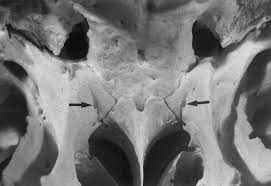

The palatovaginal canal (also pharyngeal canal) is a canal between the sphenoid bone and the palatine bone that connects the nasopharynx with the pterygopalatine fossa. It transmits the pharyngeal branch of the third part of the maxillary artery (not to be confused with the ascending pharyngeal artery, a branch of external carotid). An inconstant vomerovaginal canal may lie between the ala of the vomer and the vaginal process of the sphenoid bone, medial to the palatovaginal canal, and lead into the anterior end of the palatovaginal canal.

The opening to the palatovaginal canal in the nasal cavity is located near the lateral margin of the ala of the vomer, at the roots of the pterygoid process. The other opening to the palatovaginal canal is located inferiorly and posteriorly in the pterygopalatine fossa.